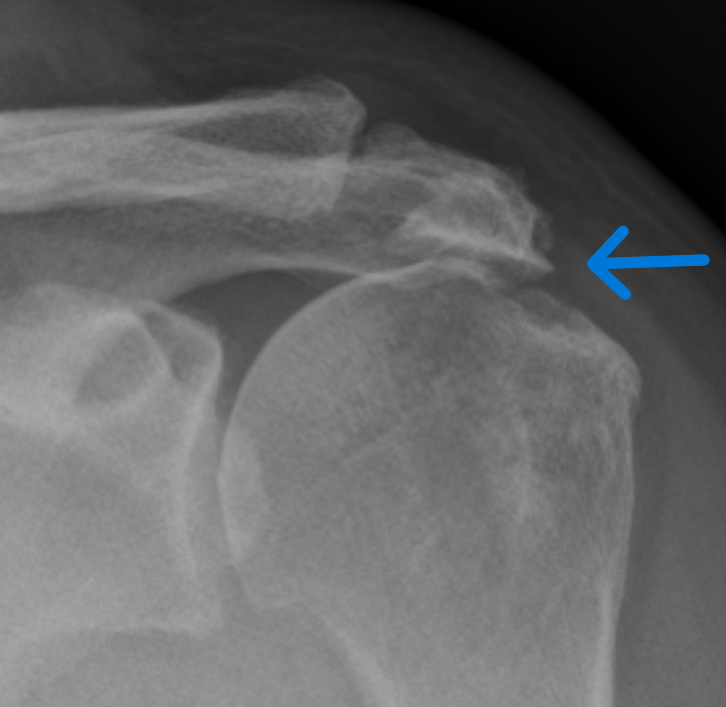

X-ray: 견봉뼈의 돌출이나 뼈 모양 이상, 관절 간격 등을 확인하여 충돌 증후군 외 다른 뼈 관련 이상 질환 감별.